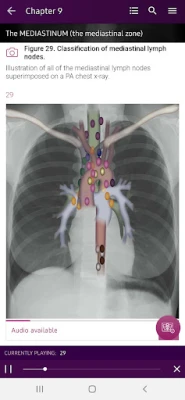

Section II* introduces the concept of radiological zones to give you a starting point in the understanding of the radiological anatomy of the chest. The next chapters review in detail the radiological anatomy of specific anatomical structures, also provide examples of how the x-ray image can change due to pathology. The final chapter explains how the individual structures come together to form the radiological image.

Radiological Anatomy – Descriptions of various anatomical structures as they would appear on PA and lateral chest x-rays.